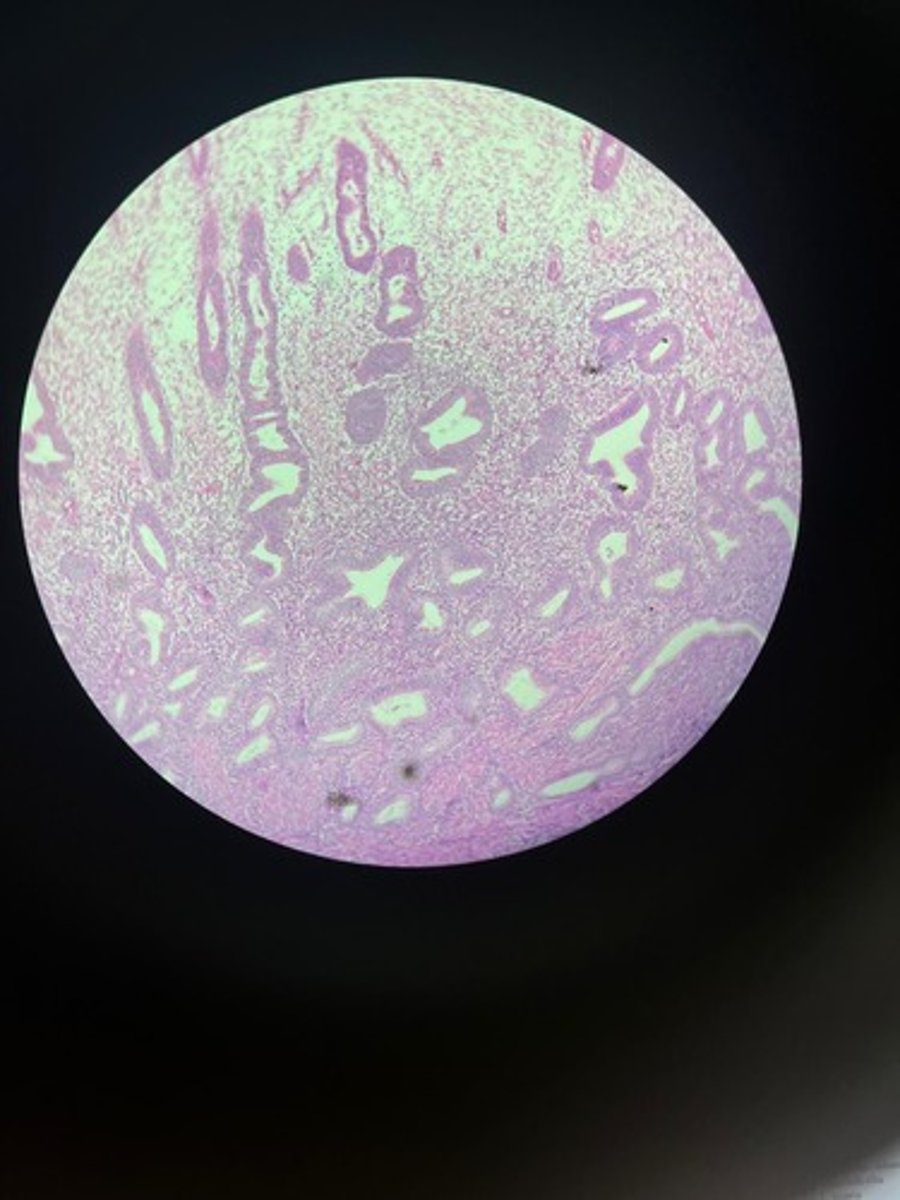

Prostate HE

Prostate HE

Prostate HE

Prostate HE